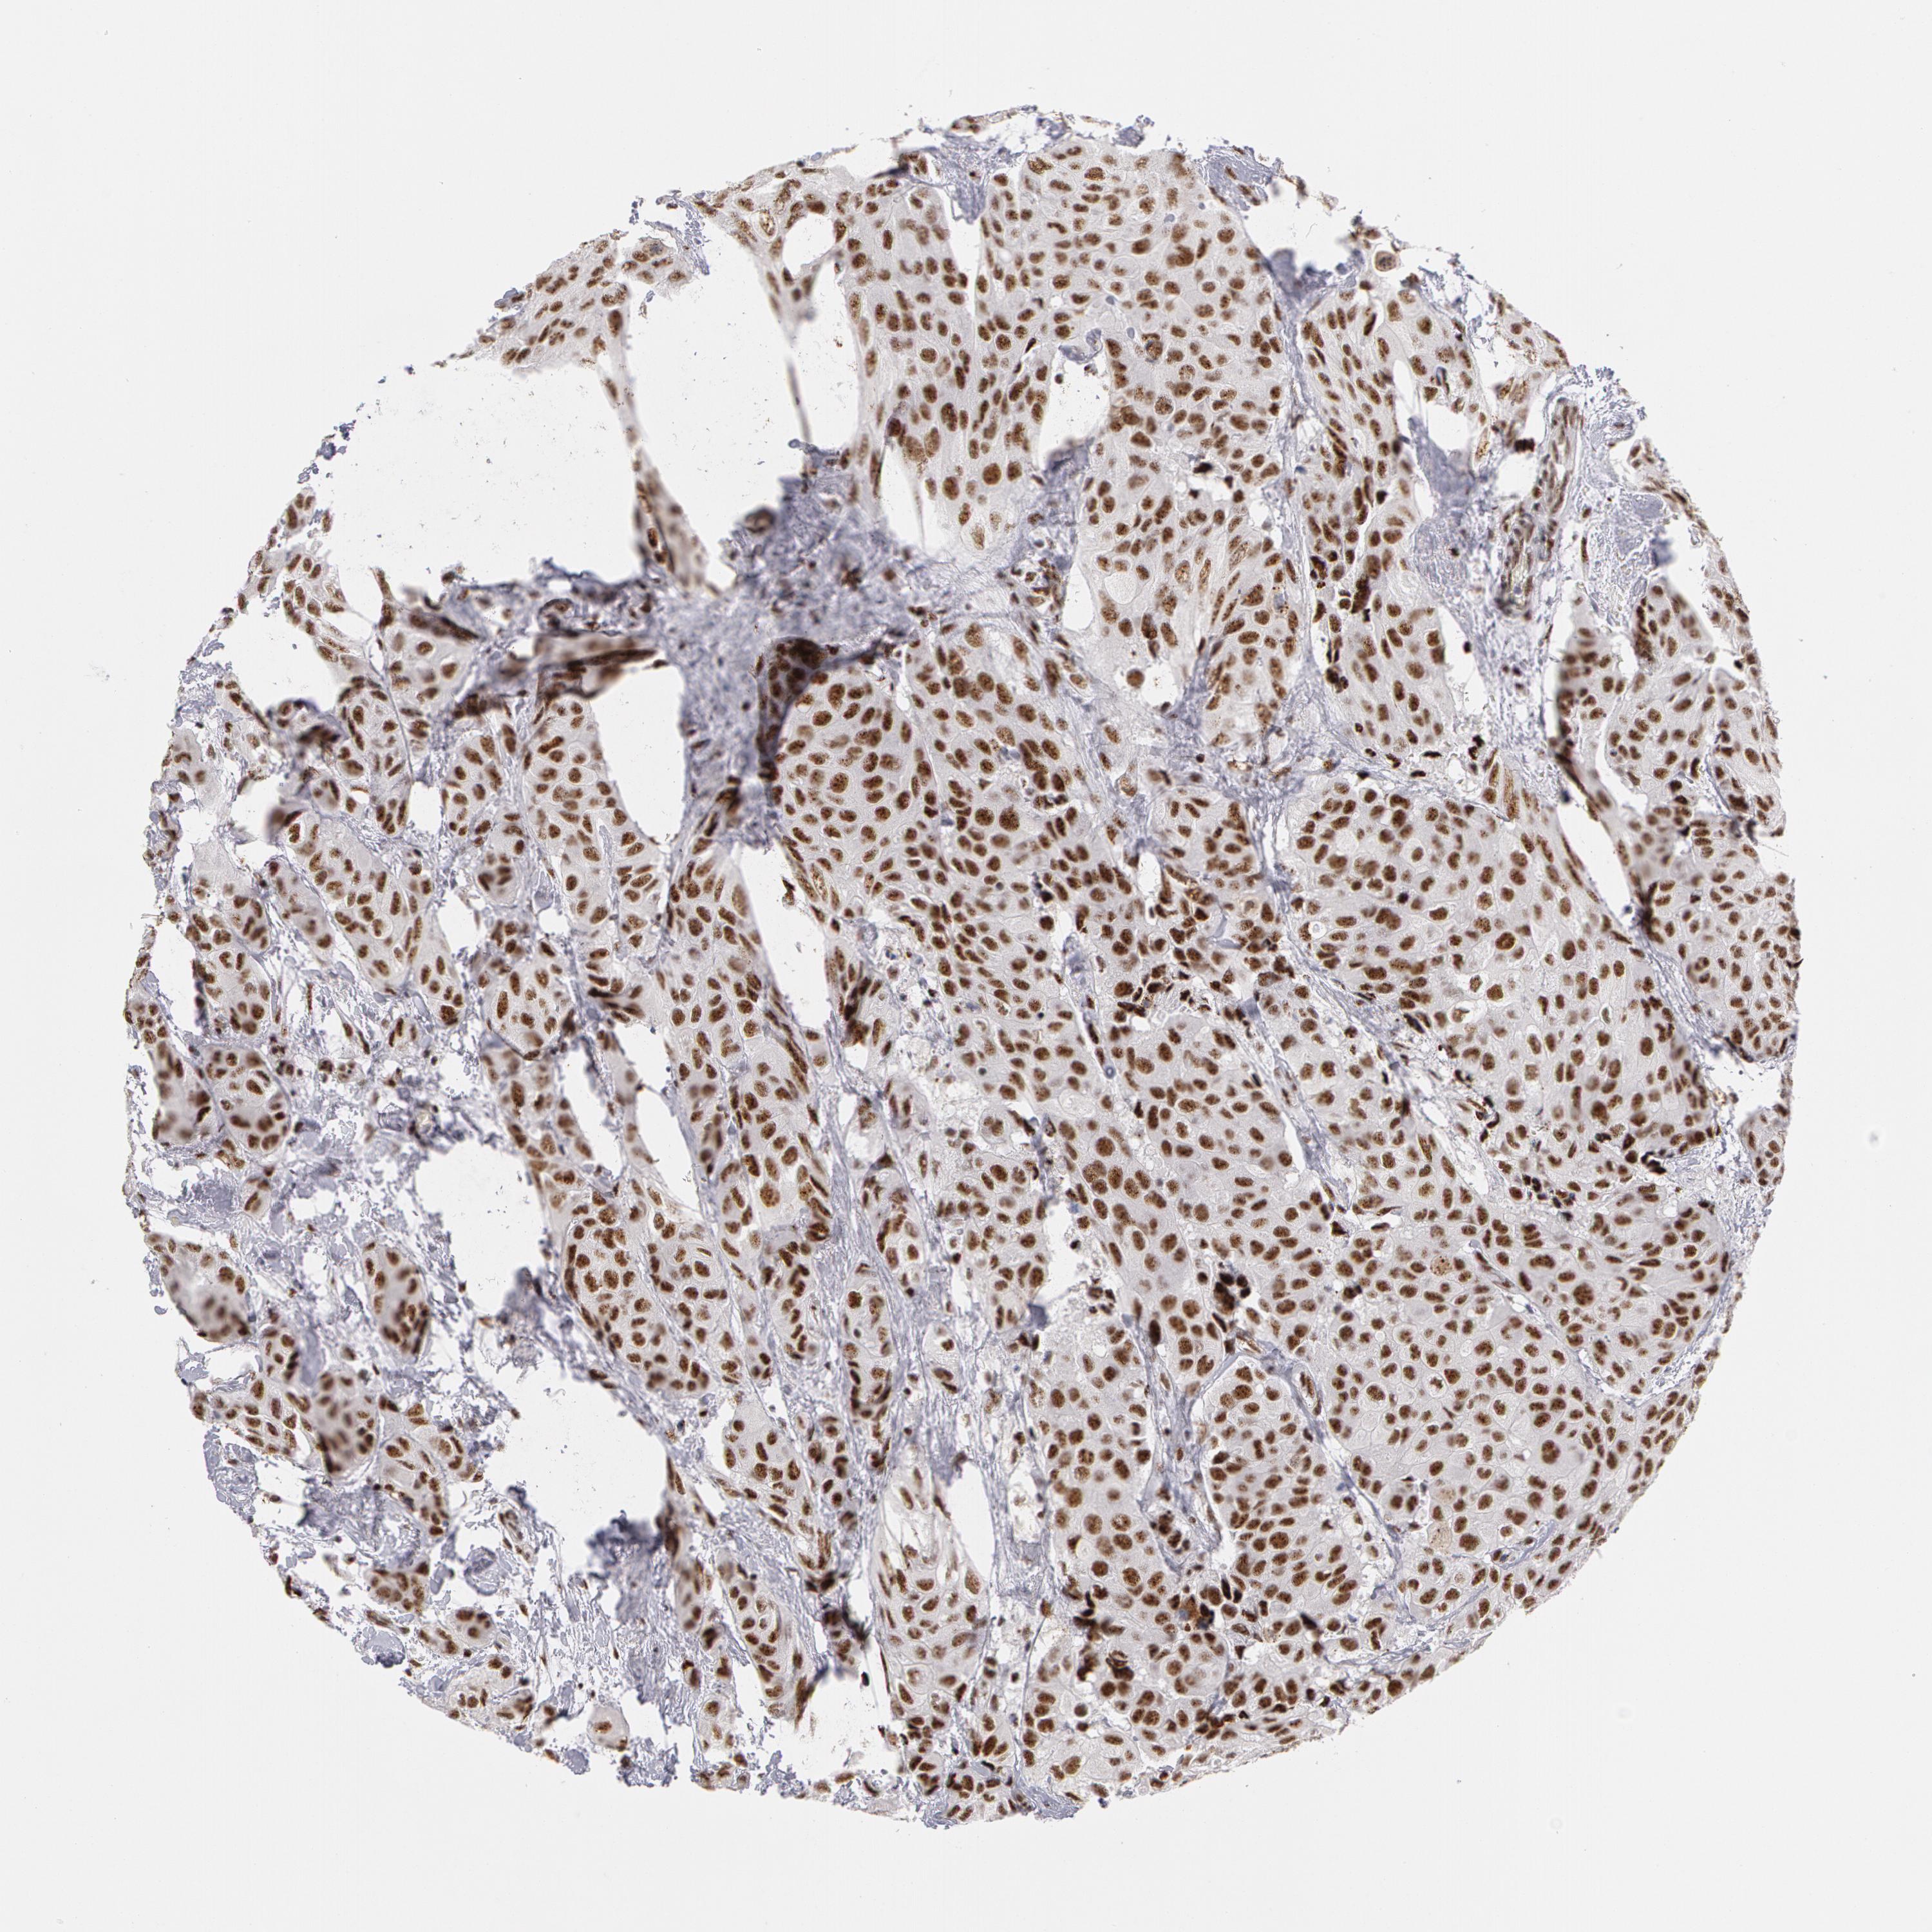

CANCER BREAST CANCER Show tissue menu

BRCA TCGA BRCA VALIDATION PROTEIN EXPRESSION

Breast cancer

Human cancer